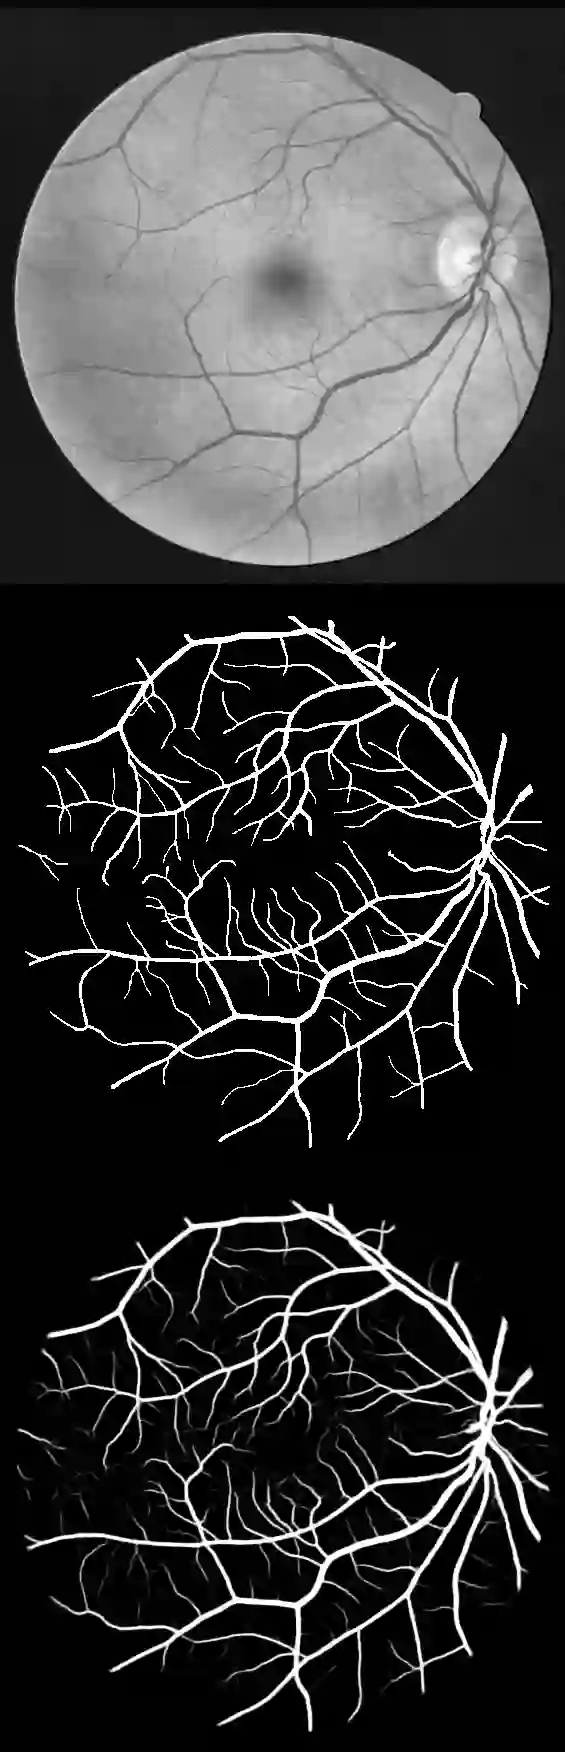

U-Net has been providing state-of-the-art performance in many medical image segmentation problems. Many modifications have been proposed for U-Net, such as attention U-Net, recurrent residual convolutional U-Net (R2-UNet), and U-Net with residual blocks or blocks with dense connections. However, all these modifications have an encoder-decoder structure with skip connections, and the number of paths for information flow is limited. We propose LadderNet in this paper, which can be viewed as a chain of multiple U-Nets. Instead of only one pair of encoder branch and decoder branch in U-Net, a LadderNet has multiple pairs of encoder-decoder branches, and has skip connections between every pair of adjacent decoder and decoder branches in each level. Inspired by the success of ResNet and R2-UNet, we use modified residual blocks where two convolutional layers in one block share the same weights. A LadderNet has more paths for information flow because of skip connections and residual blocks, and can be viewed as an ensemble of Fully Convolutional Networks (FCN). The equivalence to an ensemble of FCNs improves segmentation accuracy, while the shared weights within each residual block reduce parameter number. Semantic segmentation is essential for retinal disease detection. We tested LadderNet on two benchmark datasets for blood vessel segmentation in retinal images, and achieved superior performance over methods in the literature. The implementation is provided \url{https://github.com/juntang-zhuang/LadderNet}